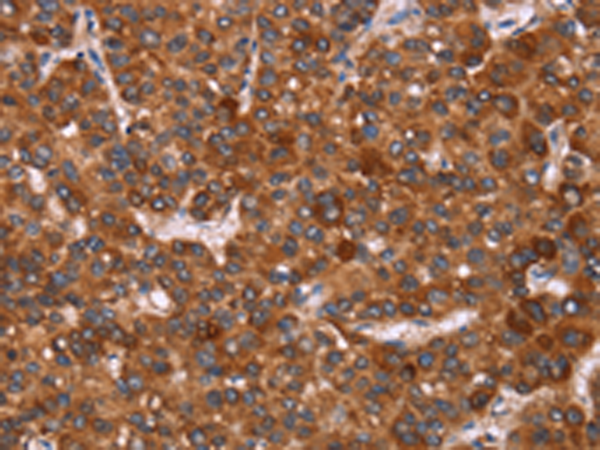

分类: 科研抗体货号: P04896别名: HGAL; GCAT2; GCET2应用: IHC反应种属: Human